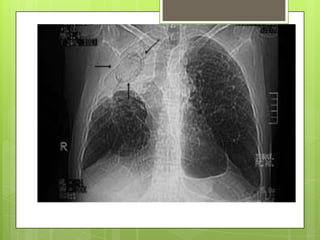

 La radiografía de tórax puede mostrar imágenes

características u otras inespecíficas.

Métodos auxiliares.  Laradiografía de tórax puede mostrar imágenes características u otras inespecíficas.  La reacción de Mantoux es habitualmente hiperérgica, aunque puede ser negativa cuando existe compromiso inmunológico (anergia).  baciloscopia directa del esputo y cultivo.  Fibrobroncoscopia permite investigar el bacilo y la presencia de gérmenes comunes y hongos  derrame pleural>> pleurocentesis pleural con agujas tipo Abrams o Cope. LP de aspecto fibrinoso.